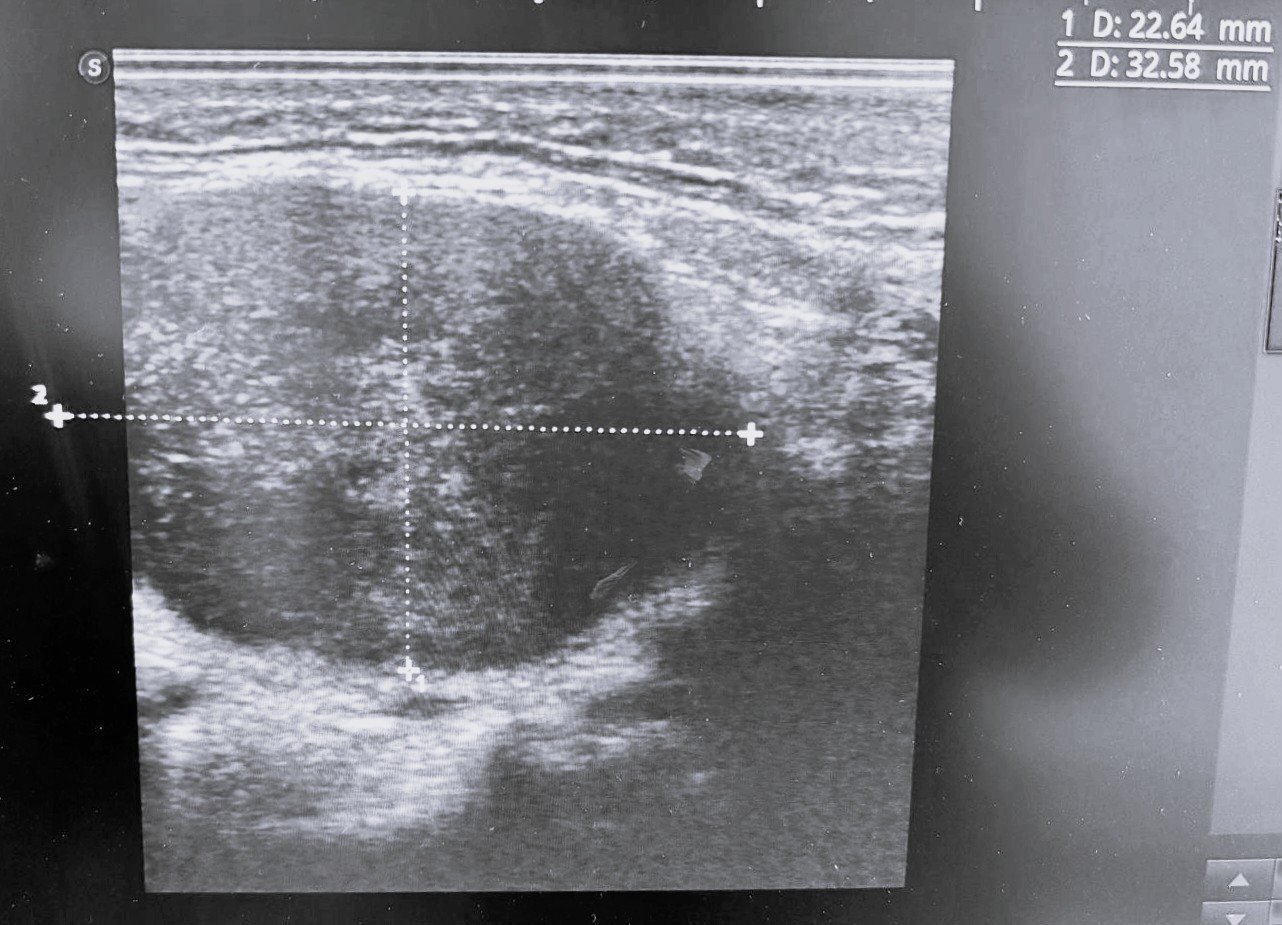

Ecografía de bultoma: se observa masa de 3x2x3 cm en área cervical III derecha, con bordes definidos, discretamente tabicada, con contenido hiperecogénico central, sin captación doppler, compatible con adenopatía patológica versus absceso.